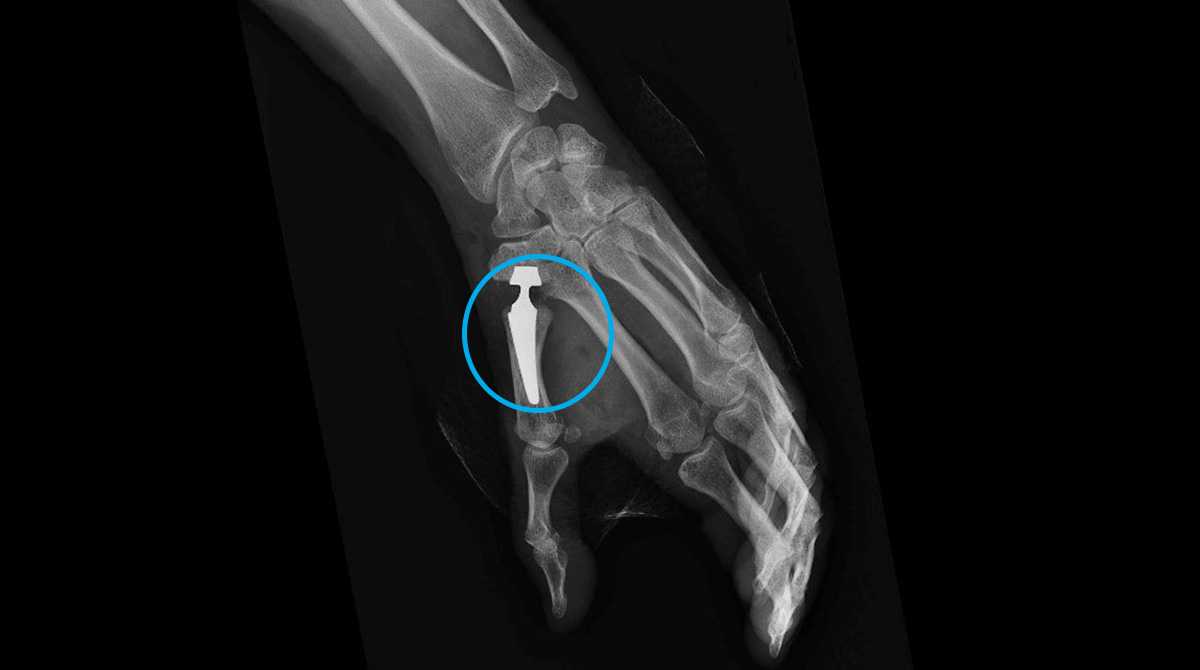

La prothèse trapézo-métacarpienne

Elle consiste à remplacer l’articulation usée par une prothèse, comme pour d’autres articulations (hanche, genou, épaule). La prothèse est constituée d’une tige implantée dans le 1er métacarpien, d’une cupule implantée dans le trapèze et d’une tête avec un col qui permet à l’implant de se mobiliser. Les développements techniques ont permis d’envisager une espérance de vie de ce type d'implant de l’ordre de 15 à 20 ans actuellement. Cette intervention n’est pas réalisable chez tous les patients selon la morphologie du trapèze et l’atteinte éventuelle de l’articulation sous-jacente.